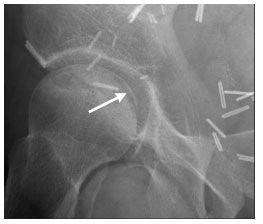

Figure 2. Lateral plain radiograph of the pelvis showing osteonecrosis with the classic "crescent" sign (arrow) of stage III disease. Surgical clips reflect previous radical cystectomy in this patient.

He has had mild, intermittent right hip discomfort for the past 6 months. Findings from previous physical examinations were unrevealing, and he retained full mechanical function, initially prompting conservative treatment with anti-inflammatory medication. A heel lift was placed in his right shoe, which offered mild relief. However, his symptoms progressed to a deep, throbbing pain radiating to his right groin, which worsened with weight-bearing activity. Plain radiographs followed by MRI of his pelvis confirmed the diagnosis of osteonecrosis (Figures 1, 2, and 3). He underwent total hip arthroplasty, with complete resolution of his symptoms.